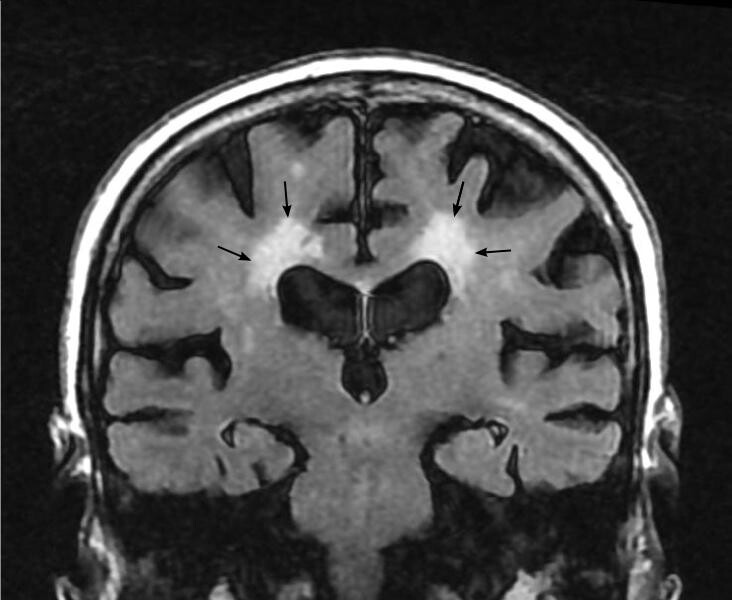

Binswanger disease subcortical arteriosclerotic encephalopathy What Is Binswanger Disease A diagnosis of binswanger's disease was proposed for our patient based on the clinical features regarding the risk factors,. Binswanger's disease (bd), also called subcortical vascular dementia, is a type of dementia caused by widespread, microscopic areas of damage to. Binswanger's disease is a rare form of dementia sometimes referred to as subcortical vascular dementia. Binswanger’s disease is a form. What Is Binswanger Disease.

Binswanger disease subcortical arteriosclerotic encephalopathy What Is Binswanger Disease Binswanger's disease is a rare form of dementia sometimes referred to as subcortical vascular dementia. Binswanger’s disease is a form of cerebral small vessels disease characterized by cognitive impairment, gait disturbances with. Binswanger's disease (bd), also called subcortical vascular dementia, is a type of dementia caused by widespread, microscopic areas of damage to. Binswanger disease is a progressive neurological disorder. What Is Binswanger Disease.